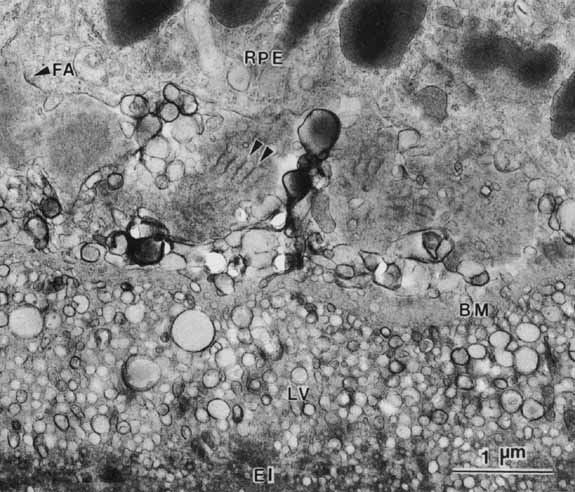

Age-related macular degeneration (AMD) is the leading cause of blindness among adults. Although the specific causes of AMD remain unknown, these include a combination of intrinsic (i.e., genetic predisposition) and extrinsic (i.e., environmental insult such as toxic and/or photooxidative damage) factors that have their primary impact on the RPE.71 AMD is associated in its early phases with the buildup of incompletely metabolized waste products in association with the RPE, both intracellularly (i.e., lipofuchsin) (Fig. 17) and extracellularly (i.e., drusen) (Figs. 18 and 19). Subsequent malfunction of the RPE proper, and/or Bruch's membrane, lead to the progression of AMD from its “dry” state with damage to the RPE and neural retina, wherein the focus of the lesion remains at the RPE/neural retina interface, to the “wet” state wherein signals that possibly originate with the RPE result in abnormal responses in surrounding tissues resulting in neovascularization in the choriocapillaris.72 Evidence to support the “toxic accumulation” hypothesis has come from studies of Stargardt's disease, a form of juvenile macular degeneration, whereby a primary defect of lipid metabolism in the neural retina leads to accumulation of toxic products following their uptake by the RPE, whose failure then subsequently leads to photoreceptor loss.73

Fig. 18 Basal surface of the retinal pigment epithelium of the macula of a 69-year-old woman. The basement membrane (BM) has been penetrated by lipid vesicles (LV) emanating from the epithelium. Deposition of material with 100-nm periodicity (arrows) increases the distance between the epithelium and its normal basement membrane. The focal adhesion (FA) exists between the epithelium and this newly deposited material (El, elastic lamina of Bruch's membrane; ×24,500).